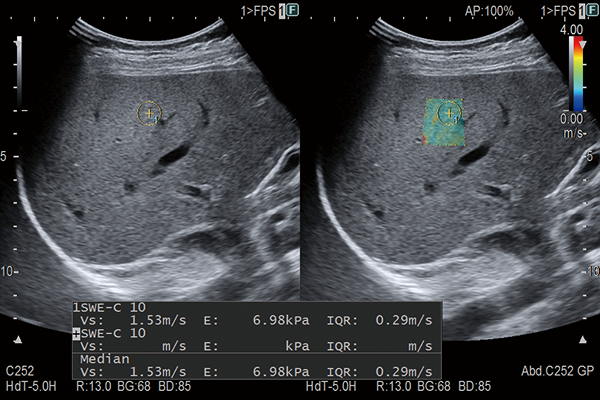

Shear waves are generated using a ‘push pulse’ to excite the tissues. SWM provides an assessment of tissue stiffness by calculating Vs, the propagation velocity of the shear waves. SWM provides an additional reliability indicator, VsN, as an objective evaluation of the Vs measurement. SWE color-codes tissue sttifness based on the propagation velocity of shear waves. SWE can be used to evaluate liver visually and non-invasively.